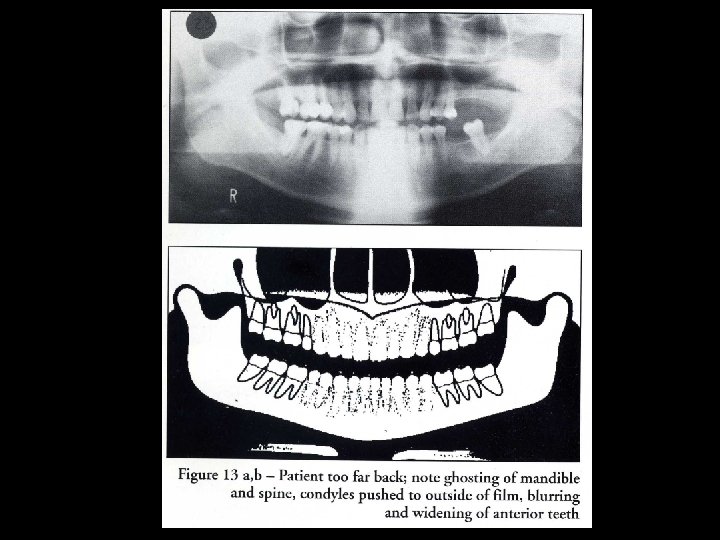

Ghost image